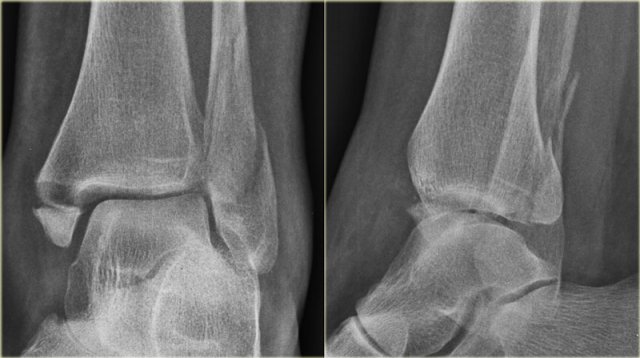

Example 4

• Basic interpretation

Fracture of the lateral malleolus starting anteriorly at the level of the joint extending proximally posteriorly.

• Classification

The fracture is classified according to Weber as a type B fracture.

According to Lauge Hansen the oblique fibular fracture indicates that this is a Supination Exorotation injury stage 2 or higher.

• Re-examination

Look for stage 3 and stage 4.

There are subtle findings which indicate a fracture of the posterior malleolus. Normally you probably would not have noticed these.

On the lateral view the posterior cortex of the tibia is interrupted indicating a fracture (blue arrow).

Even on the AP-view there are subtle findings that indicate a fracture (red arrows).

There is a widened medial clear space, which indicates a rupture of the medial collateral band, i.e. stage 4.

• Final report

Weber B fracture. According to Lauge-Hansen this is a SER stage 4.

This is an unstable fracture with dislocation that needs surgical repair.